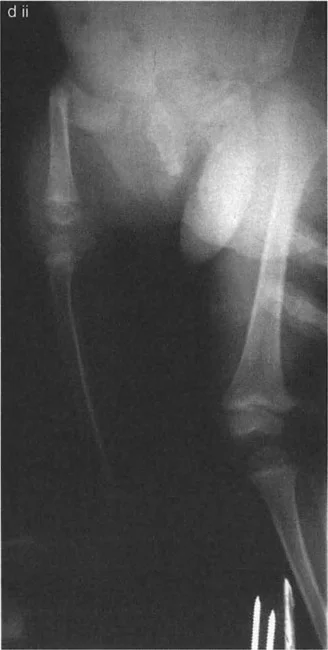

جراحة عظم الفخذ الفحجاء (Valgus Osteotomy) لتصحيح الورك الفحجاء (Varus Deformity)

تُجرى هذه الجراحة عندما يكون عنق الفخذ مائلاً جدًا للأسفل (الورك الفحجاء). تهدف العملية إلى زيادة زاوية عنق الفخذ، مما يجعلها أكثر عمودية.

جراحة عظم الفخذ الروحاء (Varus Osteotomy) لتصحيح الورك الروحاء (Valgus Deformity)

تُجرى هذه الجراحة عندما يكون عنق الفخذ مائلاً جدًا للأعلى (الورك الروحاء). تهدف العملية إلى تقليل زاوية عنق الفخذ، مما يجعلها أكثر أفقية.

تأثير التشوه على المدور الكبير